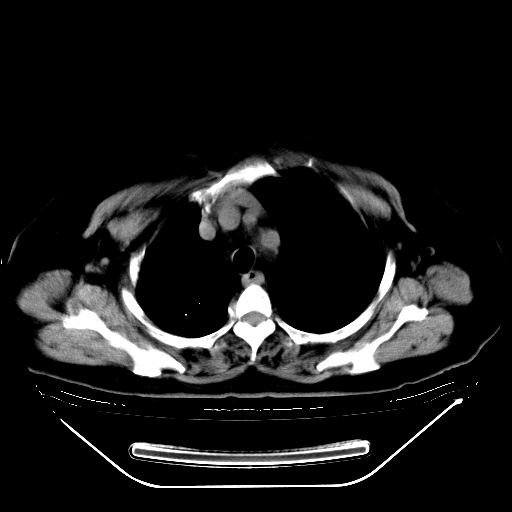

标题: CT24019:男,45岁,发现颈部肿物5个月。 [打印本页]

男,45岁,发现颈部肿物5个月,彩超示:双侧颈部及下颌部软组织增厚。

考虑双侧颈项部良性对称性脂肪增多症。